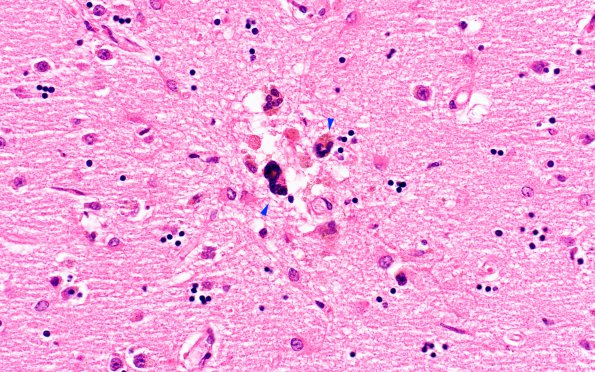

Microscopic infarct with several morular cells (arrowheads) (H&E)